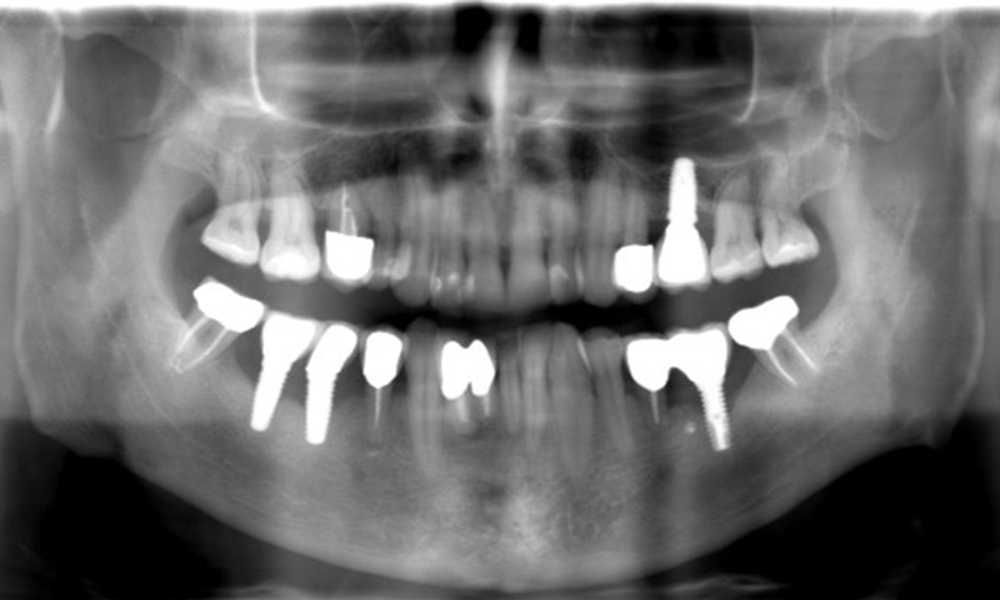

52-годишен пациент се явява на профилактичен преглед. Пациентът няма хронични заболявания и не приема никакви лекарства. Претърпял е различни дентални лечения и също така има две активни кариозни лезии. Освен това има четири импланта (2-ри, 3-ти и 4-ти квадрант). Установява се, че има ранно пародонтално заболяване (стадий IV, степен В). Състоянието на пародонта е стабилно, като дълбочина на сондиране (ST) от 5 mm се проявява само при импланта в област 36. Установен е и гингивит.

Рентгеновите снимки показват прогресията на костната загуба. ОПГ от 29.06.2020 г. (вляво) и ОПГ от 26.02.2024 г. (вдясно).

Рентгеновите снимки показват прогресията на костната загуба.